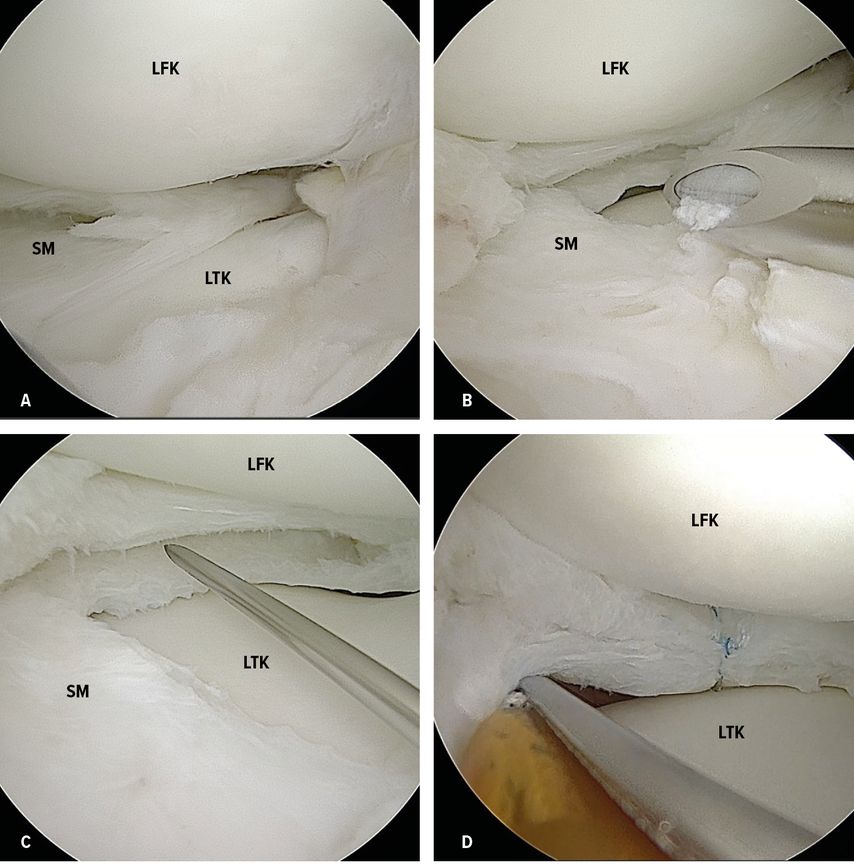

Beim arthroskopischen Meniskuserhalt erfolgt in einem ersten Schritt die Teilmeniskektomie oder sogenannte „Saucerization“. Der zentrale Teil des Scheibenmeniskus soll dabei rückgekürzt werden und so die physiologische Form wiederhergestellt werden (Abb. 4A–C). Es ist darauf zu achten, dass genügend peripherer Rand stehen gelassen wird. Hier werden 6–8mm empfohlen, weniger als 5mm könnten degenerative Veränderungen begünstigen.11,25,26

Abb. 4 A–D: Arthroskopie eines rechten Kniegelenks mit anterolateralem Zugang als Kameraportal und anteromedialem Zugang als Instrumentenportal. A: Inkompletter, aufgefaserter lateraler Scheibenmeniskus. B: Teilmeniskektomie/„Saucerization“ des zentralen Anteils des Scheibenmeniskus mit horizontalem Riss. C: rückgekürzter Scheibenmeniskus mit ausreichend Rand von ca. 6–8mm. D: Setzen einer vertikalen „All-inside“-Naht. LFC: lateraler Femurkondylus, LTK: lateraler Tibiakondylus, SM: Scheibenmeniskus

Die Entscheidung für die Durchführung einer Meniskusnaht oder -resektion ist abhängig von Art, Größe, Meniskusqualität und Lokalisation des vorliegenden Meniskusrisses. Die häufig bestehenden Horizontalrisse sollen wenn möglich nach Anfrischen der Ränder mit Vertikalnähten versorgt werden (Abb. 4D). Ist eines der Blätter zu ausgedünnt, sollte es reseziert werden. Komplexe multidirektionale Risse oder radiäre Risse sind oftmals schwieriger zu nähen und zeigen vor allem, wenn sie peripherer liegen, eine schlechte Einheilung. Sie sind, sofern möglich, sparsam zu resezieren.19 Anschließend soll noch entlang der gesamten Zirkumferenz die Stabilität des Meniskus beurteilt werden und gegebenenfalls eine Refixation erfolgen. Die verwendete Nahttechnik zur Versorgung etwaiger Risse oder Instabilitäten ist dabei von der Lokalisation abhängig. Sind diese im Bereich des Hinter- und Seitenhorns lokalisiert, kommt sehr häufig die „All-inside-Technik“ zur Anwendung. Die Vorteile dieser Methode liegen in der geringeren OP-Dauer sowie der geringeren Morbidität, da im Gegensatz zur „Inside-out“-Methode keine zusätzlichen Hautinzisionen nötig sind. Jedoch besteht bei Kindern, gerade posterior, ein Nahebezug zu den neurovaskulären Strukturen, weshalb es sich empfiehlt, die Eindringtiefe der Applikationsnadel anzupassen.27,28 Versagen, Komplikationen und klinisches Outcome sind bei beiden Methoden ähnlich.29 Für Risse oder Instabilität, die auf den vorderen Abschnitt des Meniskus begrenzt sind, eignet sich die „Outside-in“-Nahttechnik.